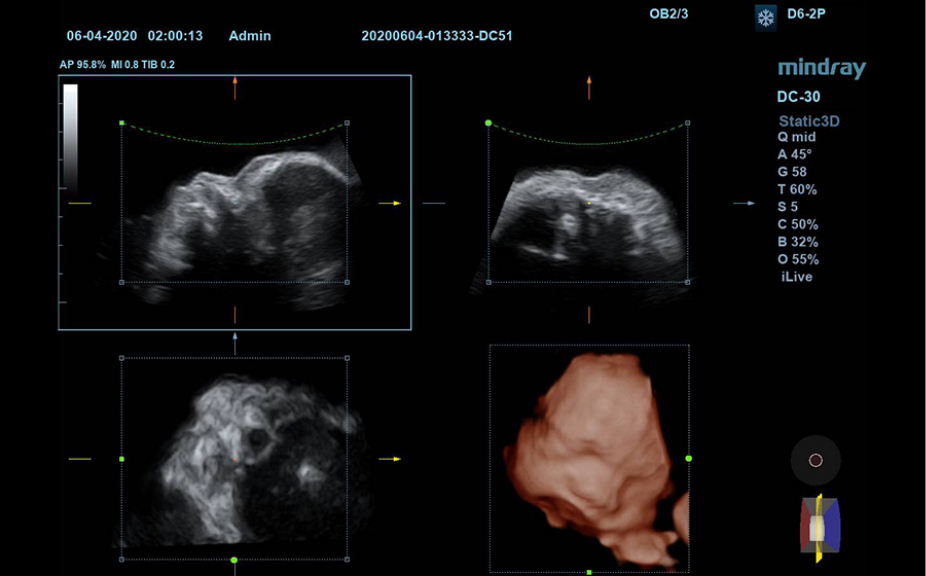

1Широкий выбор плоскостей исследования для конкретных случаев.

Пакеты плоскостей, охватывающие различные области применения: брюшная полость, акушерство и гинекология, щитовидная железа, молочная железа, яички.

Включает различные режимы визуализации.

Анатомические иллюстрации, включающие схемы и УЗИ-изображения.

Боковое отображение стандартной эхограммы, обеспечивающее визуальное наведение на изучаемую область.

Стандартные эхоизображения

3

Сравнение результатов сканирования в реальном времени для справки.

Демонстрация правильного положения пациента во время сканирования и размещения датчика.

Клинические видео

Клинические изображения